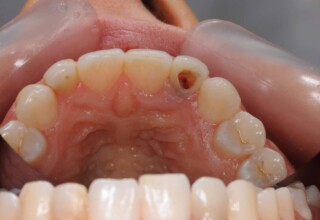

Δύσχρωμα απονευρωμένα δόντια

Μια ιδιαίτερη περίπτωση δύσχρωμων απονευρωμένων δοντιών που ο κεντρικός είχε βλάβη από εξωτερική απορρόφηση. Έγινε καθαρισμός του κεντρικού από την βλάβη και επειδή δεν μπορούσε να λευκανθεί λόγω της επαφής με τα ούλα, σφραγίστηκε σε πρώτη φάση, μετά λευκάνθηκε και στο τέλος έγινε η τελική αποκατάσταση.

Αρχική εμφάνιση

Τελική εμφάνιση